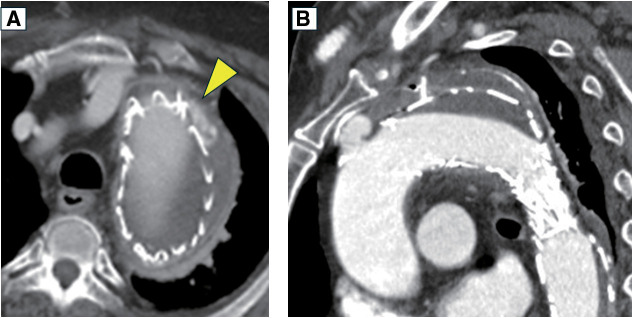

一位79岁的男性因膀胱癌经尿道切除而入院。2年前曾因Stanford B型急性主动脉夹层和胸主动脉瘤行胸血管内主动脉修复术。在住院期间,计算机断层扫描结果提出了支架移植感染的怀疑。血培养证实存在溶胆链球菌。pasteurianus。镓显像支持支架感染的诊断。随后的下消化道内窥镜检查显示下直肠结直肠癌。然后我们对支架感染进行手术治疗。

A 79-year-old man was admitted for transurethral resection of a bladder cancer. He had a history of thoracic endovascular aortic repair for Stanford type B acute aortic dissection and thoracic aortic aneurysm performed 2 years prior. During hospitalization, computed tomography scan findings raised suspicion of a stent-graft infection. Blood cultures confirmed the presence of Streptococcus gallolyticus ssp. pasteurianus. Gallium scintigraphy supported the diagnosis of a stent-graft infection. A subsequent lower gastrointestinal endoscopy revealed a colorectal cancer in the lower rectum. We then performed surgery for the stent-graft infection.